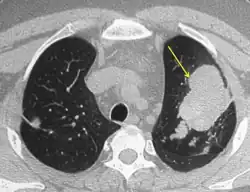

Mucoid impaction of the upper and lower airways is a common finding.[7] Plugs are hypodense but appear on CT with high attenuation (over 70 Hounsfield units[31]) in up to 20% of patients. Where present it is a strong diagnostic factor of ABPA and distinguishes symptoms from other causes of bronchiectasis.[13]

CT of the chest showing high attenuation mucous (HAM) impaction (yellow arrow). This is considered pathognomic for allergic bronchopulmonary aspergillosis (ABPA).